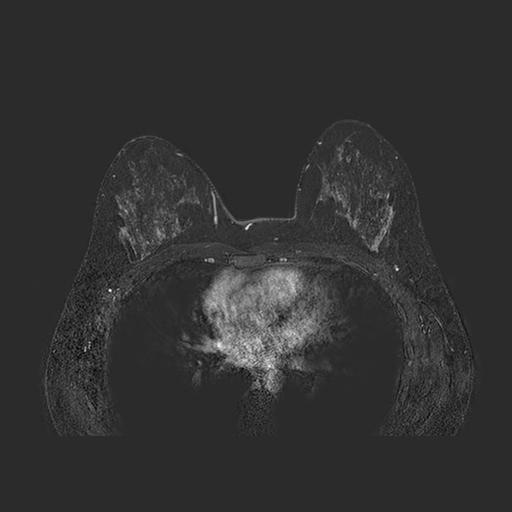

To close off this day, I also did a magnetic resonance imaging (MRI) exam with a contrast medium. The question to answer here was mainly: is my tumor a solitary lesion? or part of a bigger, scattered group? and how big is it? are my axillary lymph nodes healthy or not? This is the imaging modality for dense breast imaging: it’s also, unfortunately, very expensive.

The doctors panicked here a little bit, as the MRI showed weird inflammatory activities around my axillary zones: it turned out this was due to the double shots of vaccine I had 24 hours before (both for COVID and for the seasonal flu). Admittedly not a great timing, but I needed to help my immune system as fast as possible before starting chemotherapy. Yes, those up there are my boops as I breathe in and out on the machine. The exam was long, uncomfortable, and loud as hell.